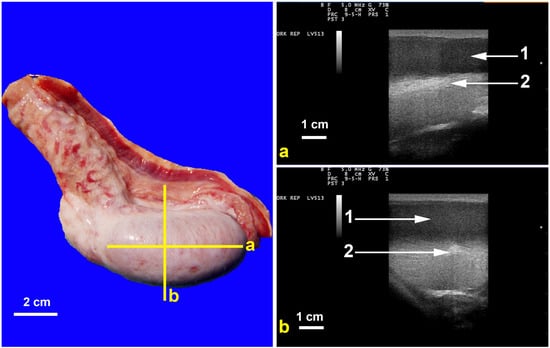

1. Introduction

3.3. Testicular and Epididymal Cysts

- Kutzler, M.A.; Shoemaker, M.; Valentine, B.A. Bilateral Cystic Rete Testis in an Alpaca (Lama pacos). J. Vet. Diagn. Investig. 2006, 18, 303–306. [Google Scholar] [CrossRef]

- Gray, G.A.; Dascanio, J.J.; Kasimanickam, R. Bilateral Epididymal Cysts in an Alpaca Male Used for Breeding. Can. Vet. J. 2007, 48, 741–744. [Google Scholar]

- Bott, I.; Pearson, L.K.; Rodriguez, J.S. Prevalence and Pathologic Features of Rete Testis Cysts in Alpacas (Vicugna pacos). Clin. Theriogenol. 2010, 2, 395. [Google Scholar]